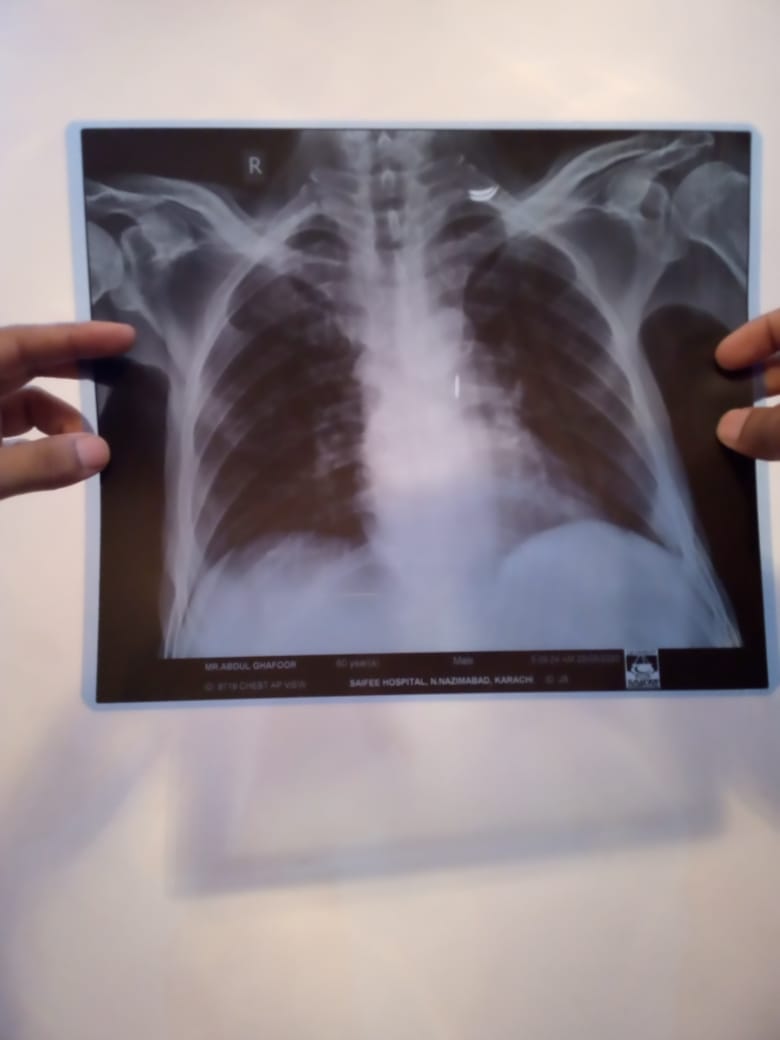

Patient was admitted in hospital due to cancer illness. He didnt have any fever or cough. The doctors performed chest X ray and determined on basis of X ray that patient has contracted coronavirus. I have attached the pictures of the X ray. Please verify if lungs are clear or not.

If they are suspecting corona ask them to do PCR test. X-ray chest is not specific for Covid. CT chest with contrast will clear the quirey

not necessary that all the patients of cancer have covid 19 but now a days it is nesccery to perform covid test of every immnocompromiz pt. Cancer is one of them . X ray chest is not normal but i m not an xray specialist. All the immunocompromised are nesccery to perform this test and indications to take precautions for doctos . If the test is positive than inform the relatives.